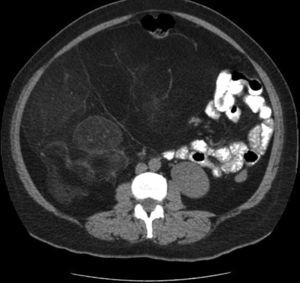

Se procede a realizar tomografía axial computarizada observándose tumor heterogéneo dependiente de retroperitoneo, el cual abarcaba más de la mitad de la cavidad abdominal (figs. 1 y 2) y era compatible con un liposarcoma. Debido a esto se programa a la paciente para tiempo quirúrgico y se realiza cirugía R0 (cirugía sin tumor macroscópico residual), realizando exéresis del liposarcoma (fig. 3), el cual se encontraba adherido al riñón derecho, por lo cual se reseca en bloque el tumor realizando nefrectomía derecha (figs. 4 y 5).